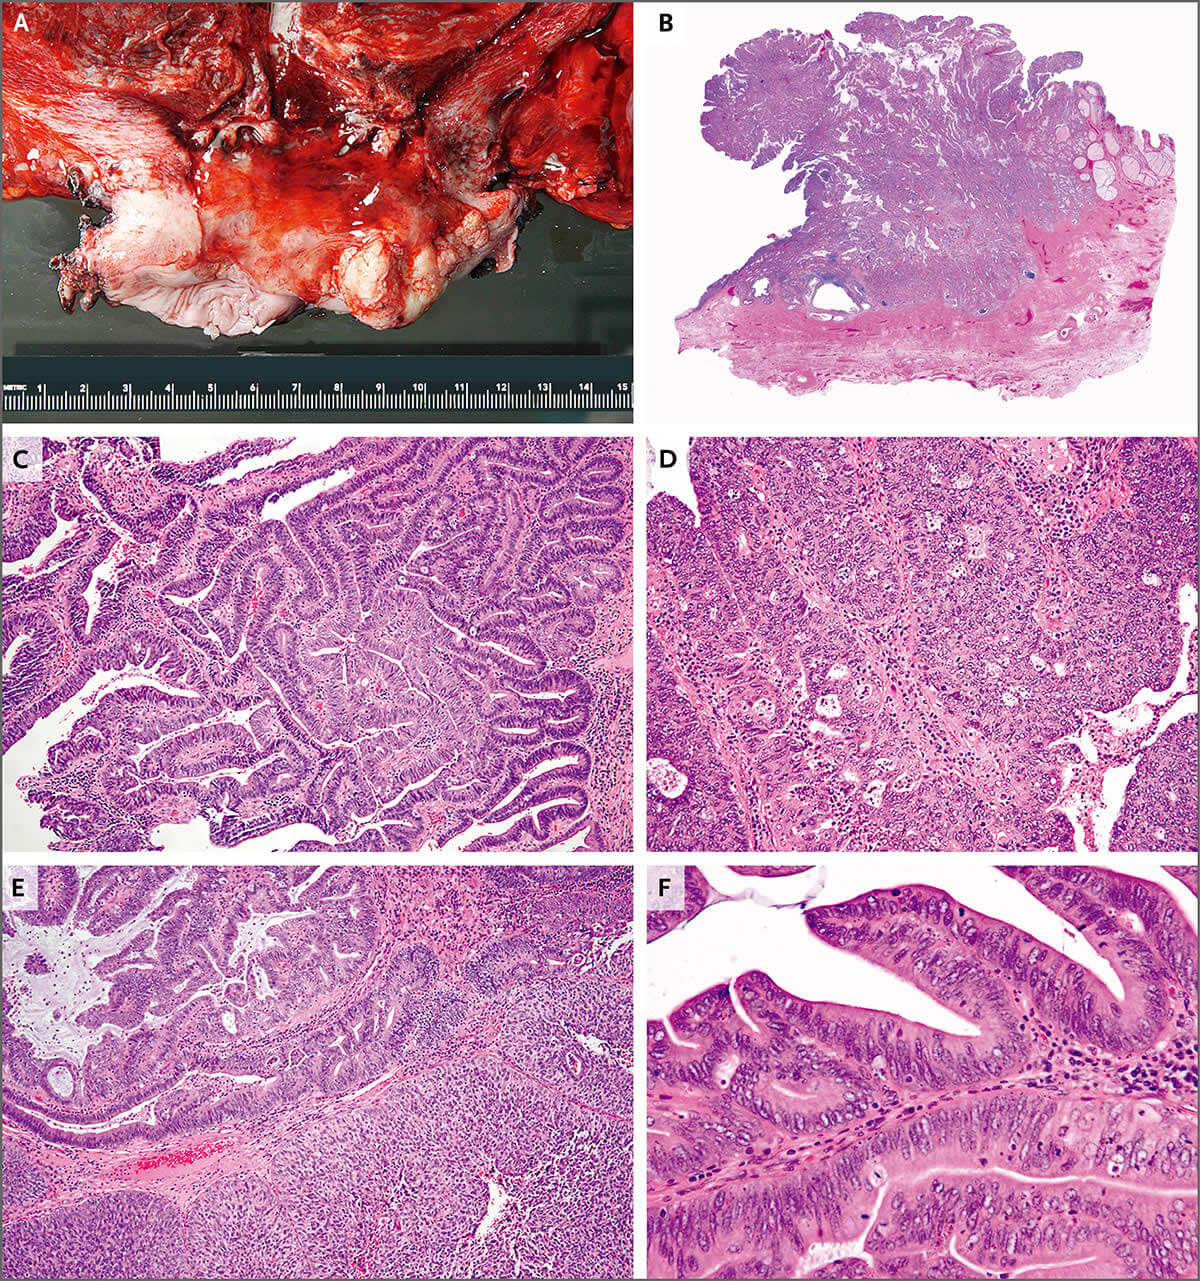

间变性大细胞淋巴瘤,ALK阳性 – 91360智慧病理网

淋巴瘤误诊为皮病性淋巴结炎1例_经典病例_医脉通

图文解析弥漫大B细胞淋巴瘤(DLBCL) – 91360智慧病理网

ALK阳性间变性大细胞淋巴瘤 – 慧海拾穗博客 – 华夏病理网博客

查宏斌:这例资料不足的淋巴结该如何处理? – 91360智慧病理网

浸润性尿路上皮癌,淋巴上皮瘤样型

肝脏淋巴上皮瘤样癌三例 – 91360智慧病理网